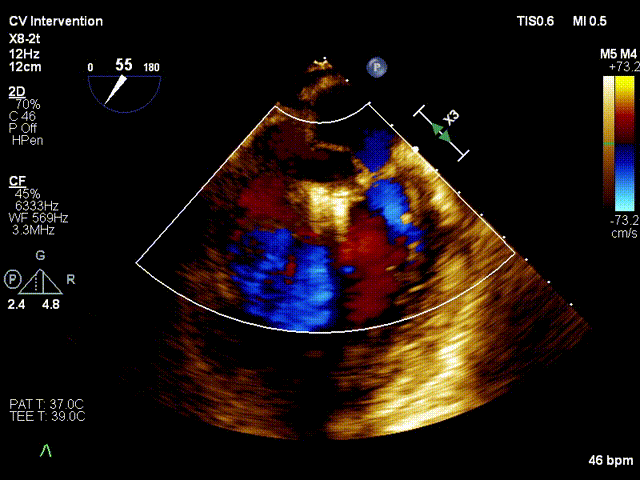

行TEE示:二尖瓣P2脱垂并累及部分P3区(DMR4+)、后叶腱索断裂、二尖瓣口舒张期几何面积 5.25cm2、收缩期二尖瓣口偏心性反流束缩流颈宽度8.0mm、PISA定量瓣口EROA=0.65cm2。STS评分13.009%。

术前X-plane